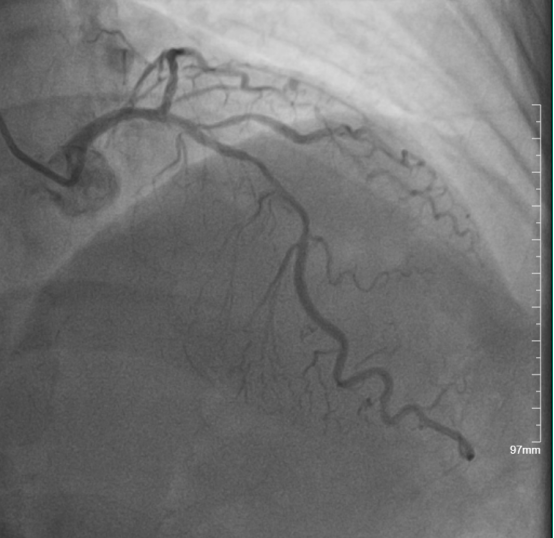

◆冠脉三支严重病变,其中右冠状动脉急性闭塞,为本次发病罪犯血管